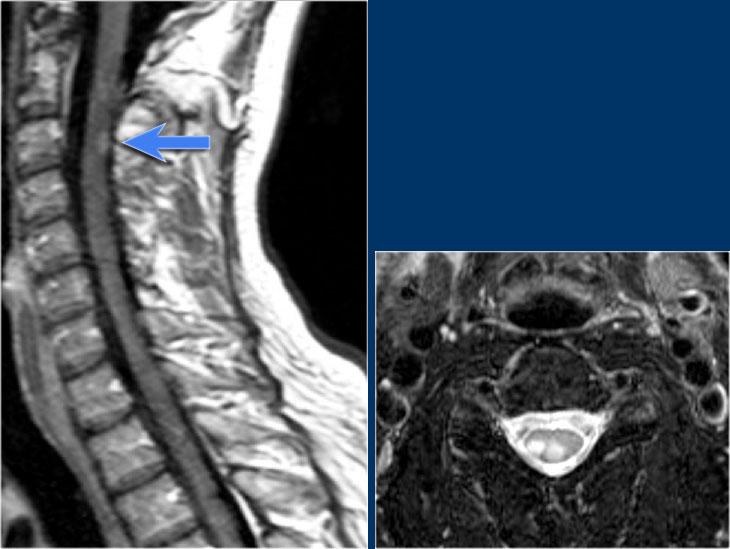

Đây là hình ảnh của một trường hợp điển hình.

Nhiều khi tiền sử lâm sàng rất hữu ích như trong trường hợp này.

Bệnh nhân nữ 24 tuổi có rối loạn thị giác một mắt, sau đó vài năm xuất hiện yếu và rối loạn cảm giác ở chi dưới và chi trên.

Hiện tại bệnh nhân đến khám vì rối loạn cảm giác ở cả hai chi dưới.

Vì vậy chúng ta đã nghĩ đến MS.

Trong tủy sống có một số tổn thương bờ rõ, nhưng cũng có một số tổn thương bờ không rõ, mờ nhạt.

Hình ảnh cắt ngang cho thấy vị trí ở phía lưng và hình dạng tam giác điển hình.

Trên các hình ảnh sau tiêm thuốc tương phản từ, không thấy ngấm thuốc.

Các tổn thương MS hoạt động ở tủy sống có thể ngấm thuốc, nhưng không phổ biến như các tổn thương hoạt động ở não.

Khi phát hiện tổn thương ở tủy sống, việc chụp thêm não cũng rất hữu ích.

MRI não cho thấy các tổn thương quanh não thất và một tổn thương ở thể chai.

Các vị trí này rất đặc trưng cho MS.